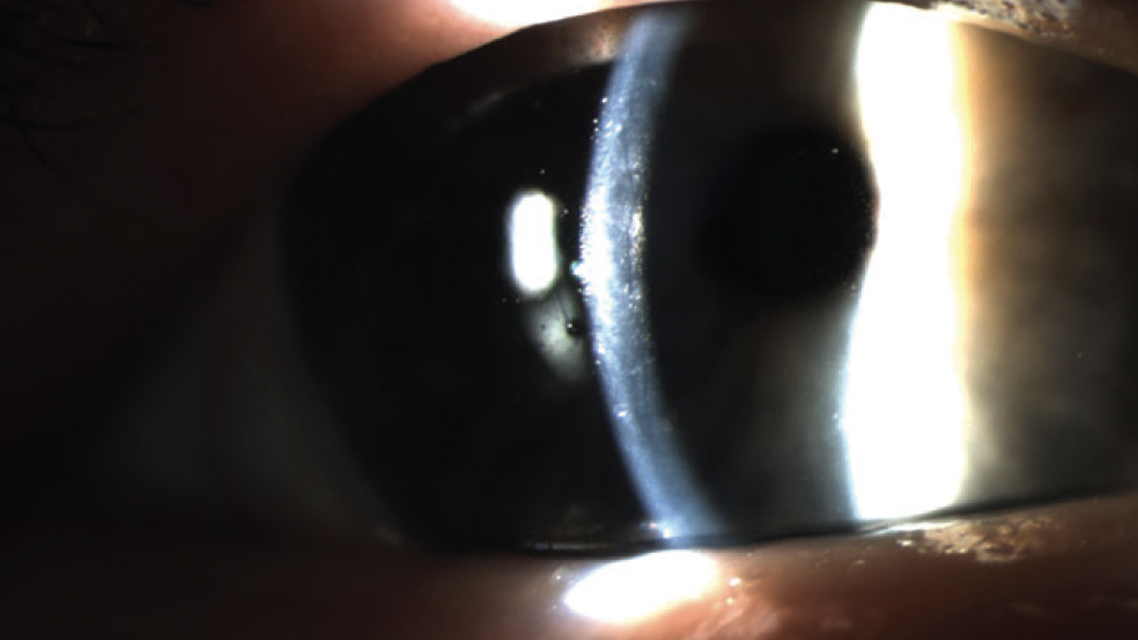

The corneal endothelium should be examined for signs of Fuchs dystrophy (Figure), Krukenberg spindles, or signs of previous iritis. Any of these diseases can delay the healing course of the eye, leading to corneal edema, high IOP, or persistent iritis after surgery. An eye with pachymetry greater than 600 µm may benefit from endothelial transplantation performed in conjunction with cataract surgery.